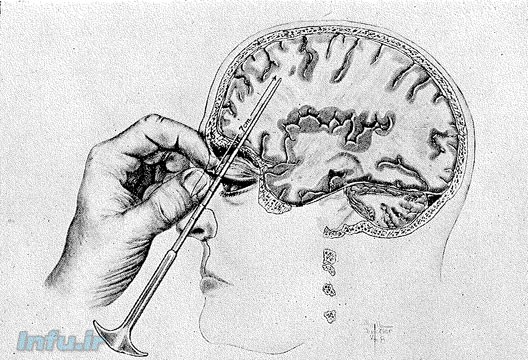

( Lobotomy) یا لوکوتومی نام نوعی جراحی افراطی و منسوخ شده بر روی مغز انسان است که در نیمه ی اول قرن بیستم به منظور درمان اختلالات روانی انجام می شد. پروسه ی خطرناک لوبوتومی که بر پایه ی ایجاد برش و آسیب تعمّدی به لوب پیشانی مغز استوار بود، معمولاً نتیجه ی معکوس و مخرب داشت و در بهترین حالت بیمار را در حالت بی تفاوتی حسی، شناختی و عاطفی نسبت به دنیای پیرامون قرار می داد. این جراحی امروزه غیرعلمی و غیراخلاقی شناخته می شود.

چیزی که در لوبوتومی اتفاق میوفتد مربوط به آسیبی است که بخش جلویی مغز میرسد، در این روش این قسمت از مغز به طور کامل تخریب میشود و ارتباط خود را با دیگر قسمت های مغز از دست میدهد، در نتیجه عکس العمل های شخص به محیط کاهش میابد و به سختی چیزی را درک میکند اما در نتیجه ی همین عوامل دیگر نشانه ای از بیماری از خود نشان نمیدهد.

پروفسور فیبرتی میگوید: لوبوتومی در ان زمان به عنوان روشی درمانی به کار میرفت به این صورت که بیمار ابتدا توسط شوک الکتریکی بیهوش میشد و در نهایت توسط یک میله و چکش برای همیشه از ادامه دادن زندگی عادیش بازمیماند، در این عمل قسمت جلویی مغز و توانایی درک به طور کامل از بین میرفت و بیمار گاها حتی دچار فراموشی دائمی میشد، لوبوتومی لکه ی ننگ علم پزشکی است.

میله ی لوبوتومی 11 سانتیمتر طول و حدود 2 سانت عرض داشت و پس از ورود به مغز به طور 15 درجه گردش میکرد با این وجود این عمل در پزشکان دیگر متفاوت بود و هرکدام روش خود را داشتند.